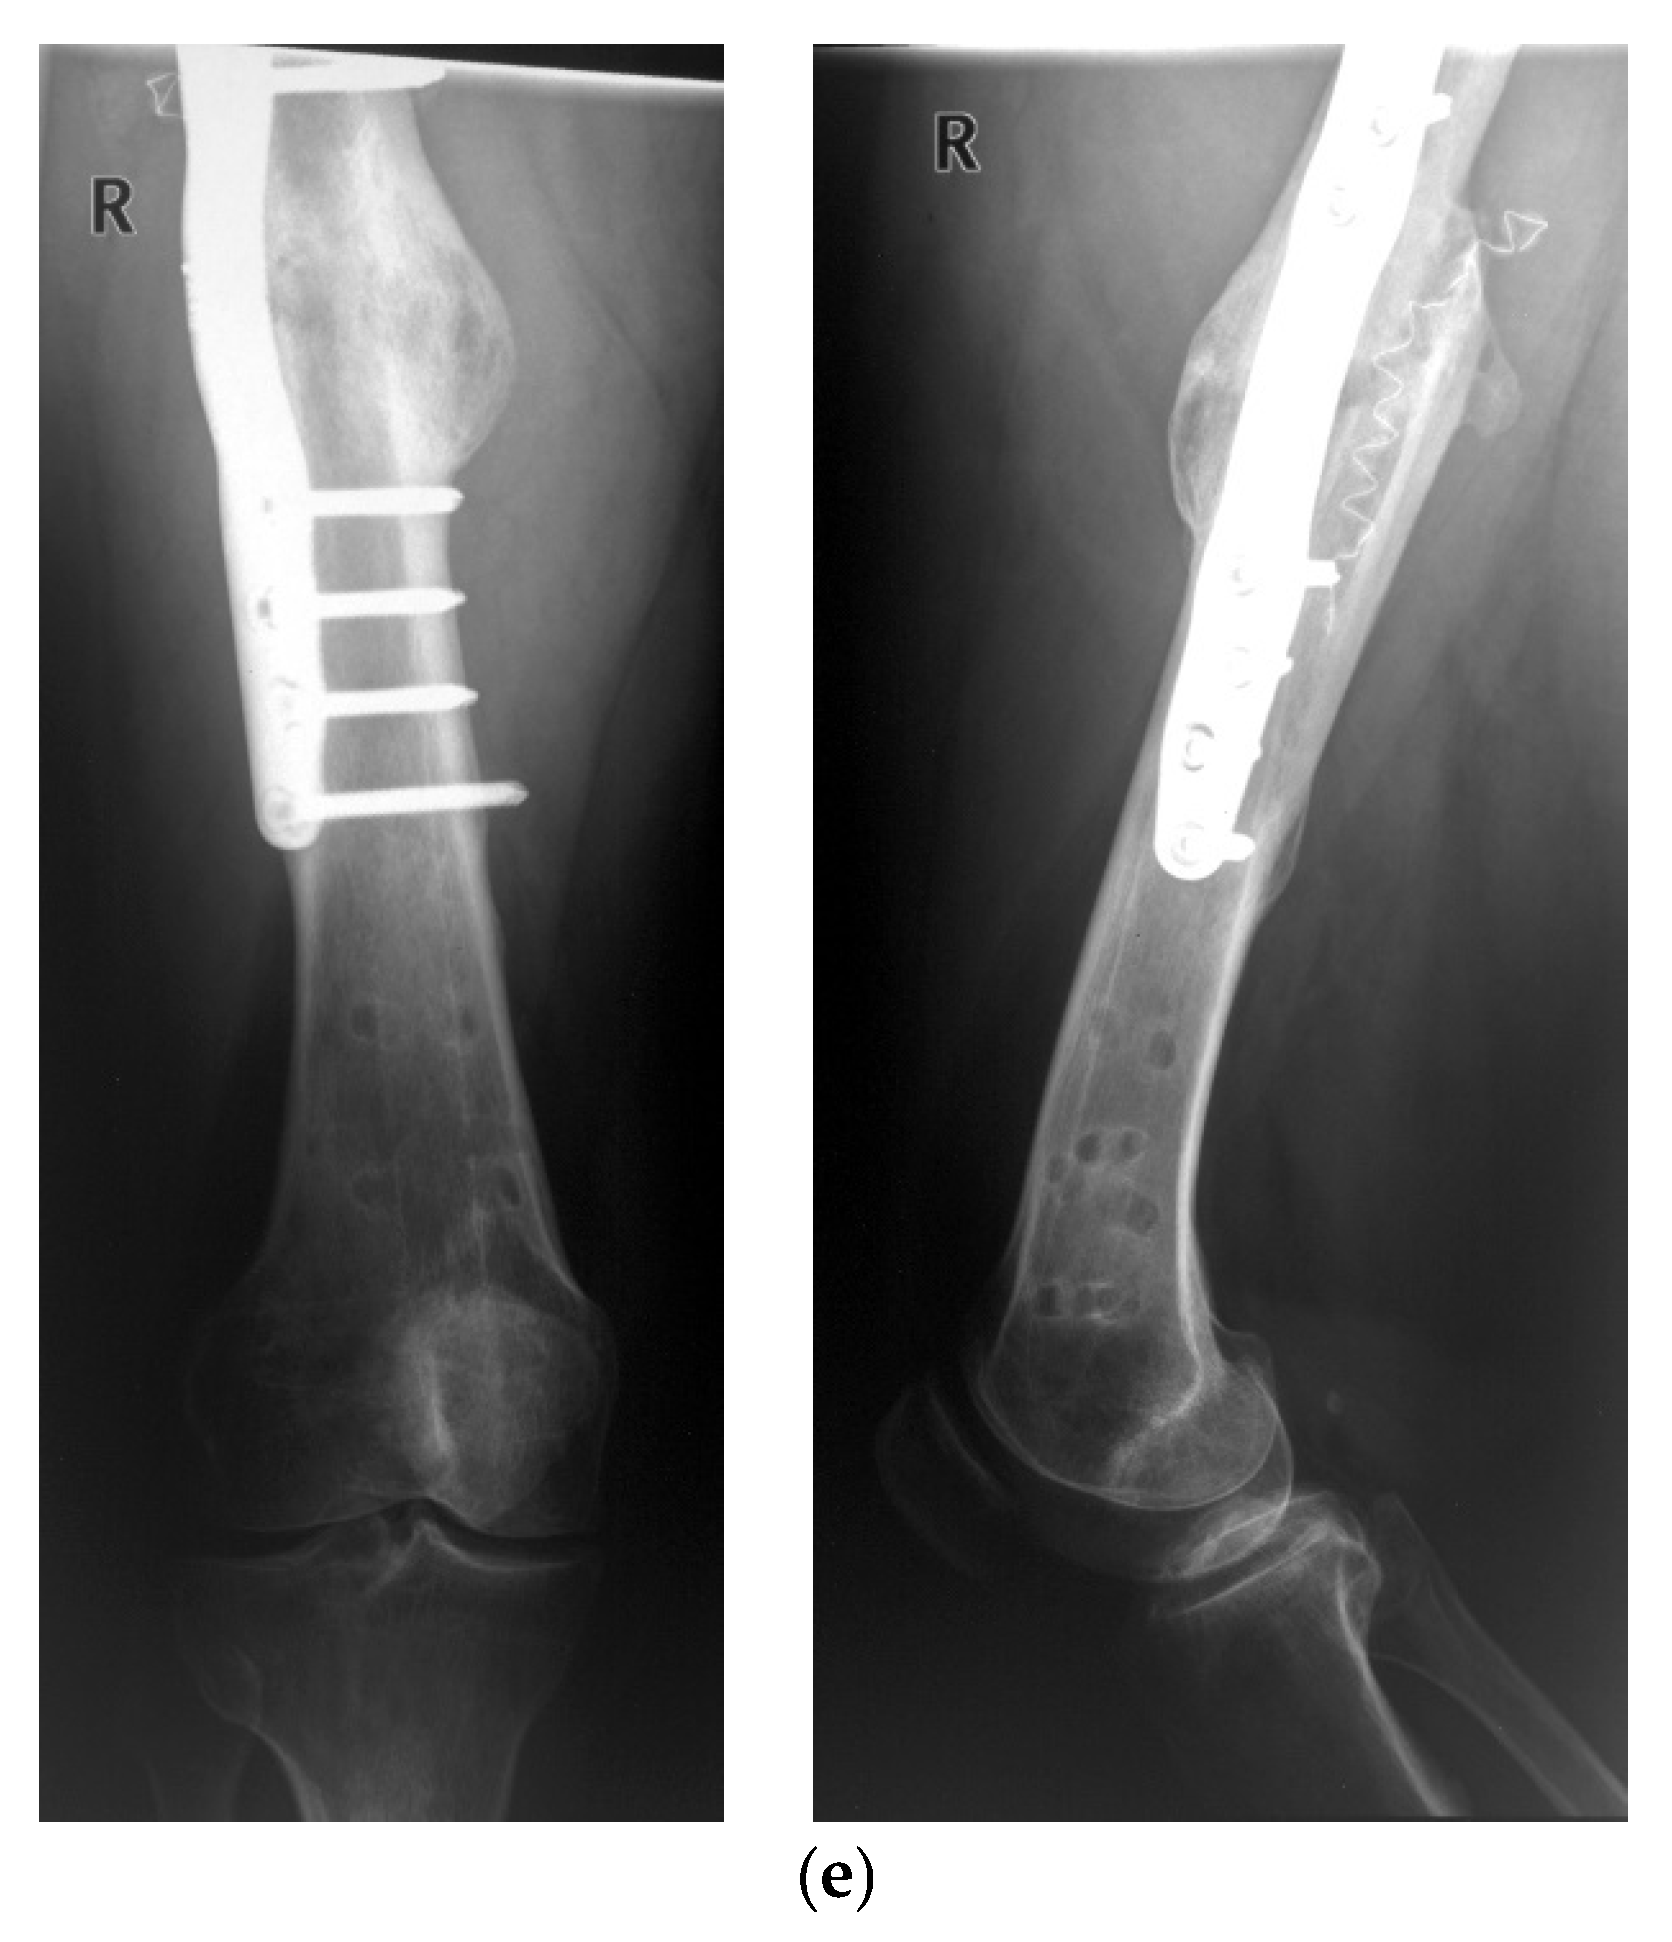

- Seide, K.; Aljudaibi, M.; Weinrich, N.; Kowald, B.; Jürgens, C.; Müller, J.; Faschingbauer, M. Telemetric assessment of bone healing with an instrumented internal fixator. J. Bone Jt. Trauma Surg. 2012, 94-B, 398–404. [Google Scholar] [CrossRef]

- Kowald, B.; Seide, K.; Auerswald, M.; Faschingbauer, M. Slow-healing non-unions. Measurement of mechanical stability with the instrumented implant. 3 case reports. Trauma Berufskrankh. 2019, 21, 181–192. [Google Scholar] [CrossRef]

- Faschingbauer, M.; Seide, K.; Aljudaibi, M.; Kowald, B.; Münch, M.; Weinrich, N.; Jürgens, C.; Moss, C.; Kirchner, R. Intelligent implants for monitoring bone healing. Trauma Occup. Dis. 2013, 15, 240–248. [Google Scholar]

- Kienast, B.; Kowald, B.; Seide, K.; Aljudaibi, M.; Muench, M.; Faschingbauer, M.; Juergens, C.; Gille, J. An electronically instrumented internal fixator for the assessment of bone healing. Bone Jt. Res. 2016, 5, 191–197. [Google Scholar] [CrossRef]